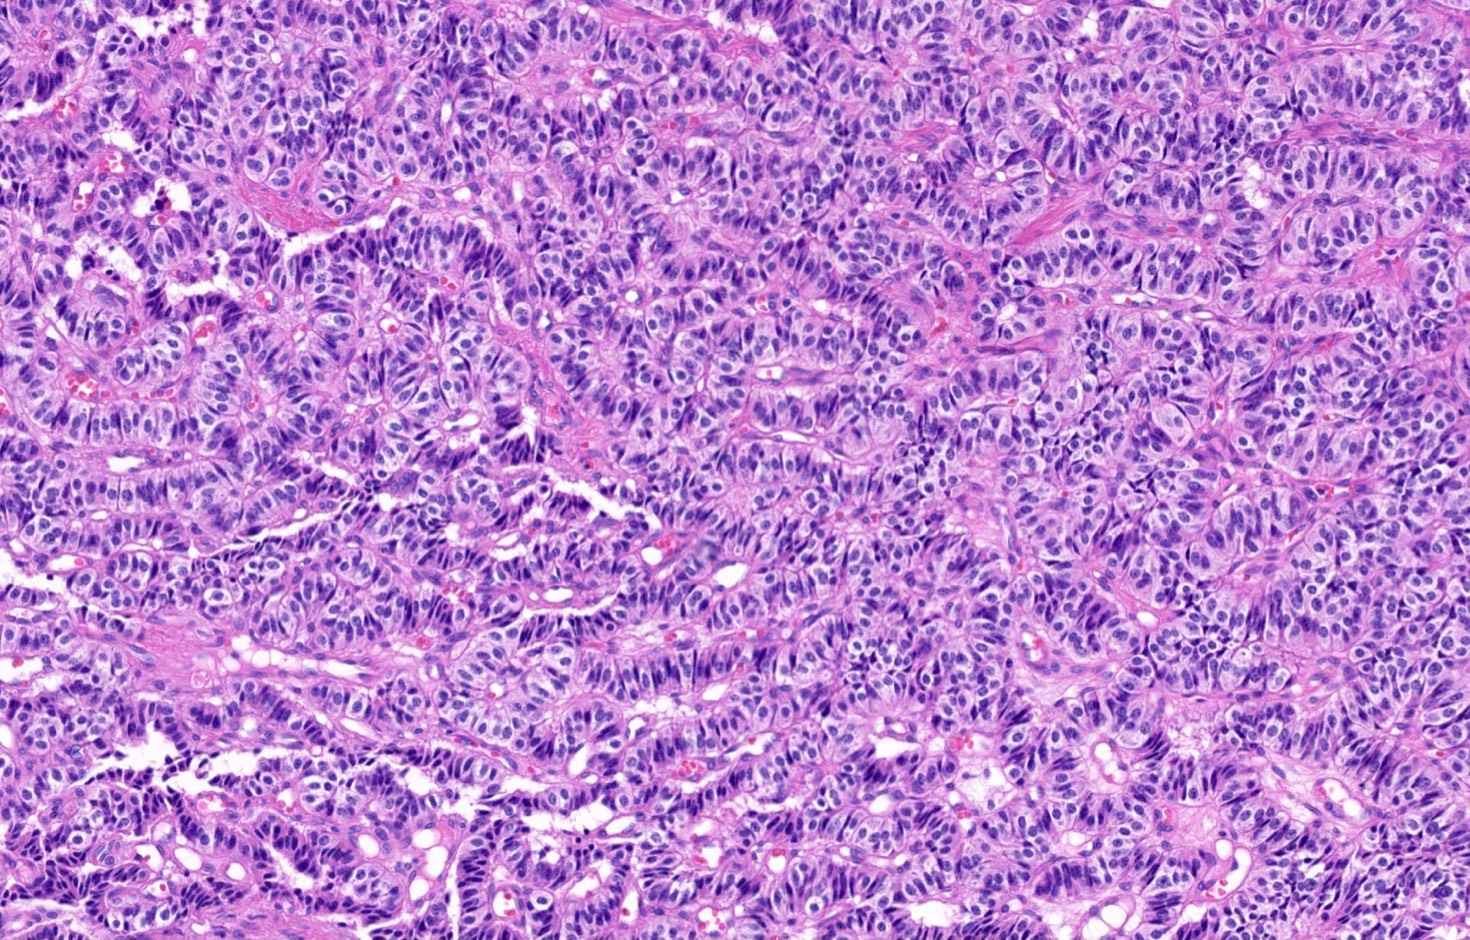

Microscopic (histologic) description

- Diagnostic criteria

- Neuroendocrine tumor with size ≥ 5 mm with < 2 mitoses/2 mm2 and absence of necrosis

- Neuroendocrine growth pattern (organoid, trabecular, rosette formation, nested) or pseudoglandular, follicular and papillary growth

- Tumor cells are uniform with a polygonal shape, round to oval nuclei with salt and pepper chromatin as well as inconspicuous nucleoli and moderate to abundant eosinophilic cytoplasm

- Spindle cells and clear cell features can be seen

- Stroma is fine and highly vascularized; hyalinization, cartilage or bone formation are possible

- Reference: Curr Oncol 2018;25:S86

Microscopic (histologic) images

Contributed by Philippe Joubert, M.D., Ph.D., Jijgee Munkhdelger, M.D., Ph.D. and Andrey Bychkov, M.D., Ph.D.

A 55 year old woman had a lower left lobectomy showing a well circumscribed flesh colored tumor. Histologic details are shown in the image above. Regarding this entity, which of the following statements is true?

Practice answer #1

A. CDX2 is usually negative in the lung and is useful to differentiate from a metastasis of an intestinal origin. The image shows a tumor with a trabecular pattern and pseudorosettes. The stroma is highly vascularized. Tumor cells are monotonous with scant to moderate eosinophilic cytoplasm. Nuclei are round to oval with salt and pepper chromatin and inconspicuous nucleoli. No mitoses are seen. These features are consistent with a typical carcinoid lung tumor.

Ki67 immunostaining, counter to well differentiated neuroendocrine tumors from the gastrointestinal tract, is not essential to grade the tumor. The difference between typical and atypical tumor relies on mitosis count and the presence of necrosis. However, Ki67 is useful to differentiate from high grade neuroendocrine tumors (small cell and large cell neuroendocrine carcinomas) on small biopsies with artifacts. TTF1 is positive in only half of cases with a higher frequency in peripheral tumors. Rb expression is preserved in typical carcinoid lung tumors, unlike in small cell tumors.